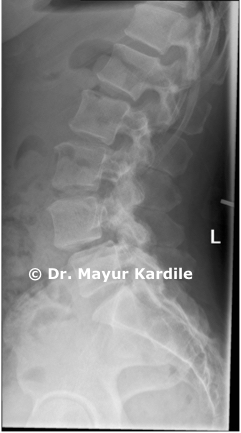

Degenerative Listhesis (also called degenerative spondylolisthesis) is slippage of one spinal vertebra over another due to degenerative changes in the disc and facet joints. Unlike isthmic spondylolisthesis which occurs in younger patients, degenerative listhesis usually affects people over 50 years of age. It commonly affects the L4-L5 level of the lumbar spine.

Case Images